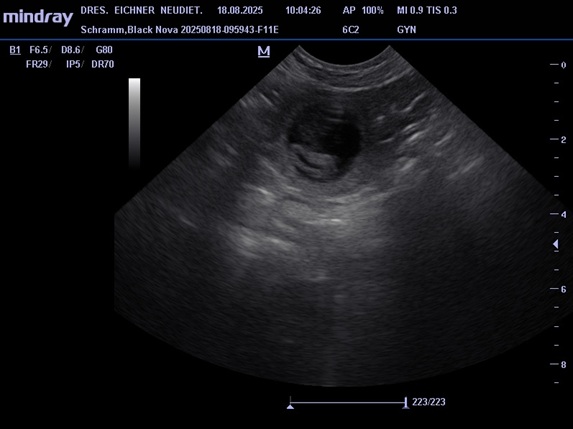

Unsere jüngsten Hündin Black Nova hatte ihr erstes Date mit Pepe am 19. 07. 2025. Pepe ist ein kräftiger kompakter Rüde mit sehr guten Gesundheitswerten. Die zwei haben sich beim Date und auch schon bei einem vorhergehenden Treffen gleich verstanden. Am 18.07. waren wir dann beim Ultraschall, das Ergebnis war positiv, somit erwarten wir Mitte September kleine Bullis in unseren Kennel. In der Nacht vom 20. zum 21. 09. 2025 sind 7 kleine Apfelknirpse bei uns gelandet, 4 Rüden und 3 Hündinnen. Nova und den Welpen geht es gut alle sind wohlauf. Alle Knirpse haben ihr Zuhause gefunden und sind ausgezogen.